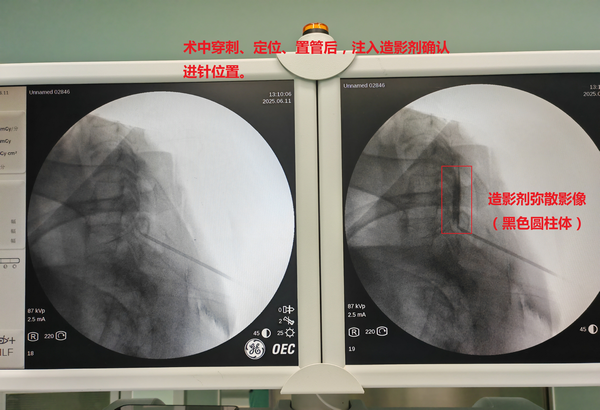

病人术中影像资料